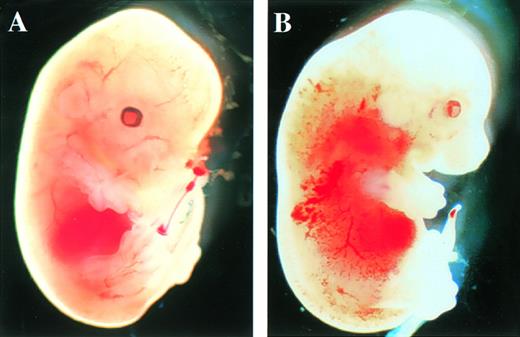

After the intercrossing of heterozygous mice, the genotypes of their litters were examined at 4 weeks of age by Southern blot analysis (Fig1B), and no homozygous mice were found. Because we did not observe the death of mice until 4 weeks of age, homozygous mice seemed to be lethal during gestation. To determine when embryonic lethality occurred, we analyzed embryos at various stages of gestation (Table 1). At E14.5, we observed no live homozygous embryos. At E12.5, some of the homozygous embryos were dead, as ascertained by the absence of heartbeat at the time of dissection. Therefore, we concluded that homozygous embryos died at E11.5-14.5. The appearance of homozygous embryos at E12.5-13.5 was edematous, with bleeding apparent under the skin (Fig 2).

Appearance of embryos at E13.5. (A) Wild-type littermate. (B) Appearance of the homozygous Mll embryo. Subcutaneous edema and hemorrhage are seen.